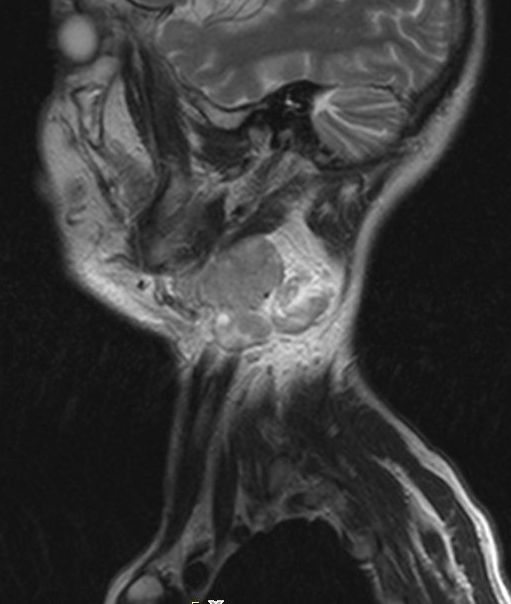

Tonsillentumor asymptomatisch. Das große Lymphknotenpaket am Unterkieferwinkel war aufgefallen.